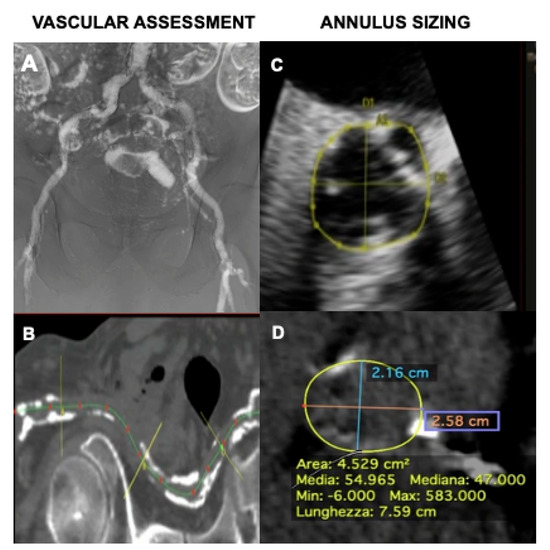

2.1. Zero-Contrast Arm